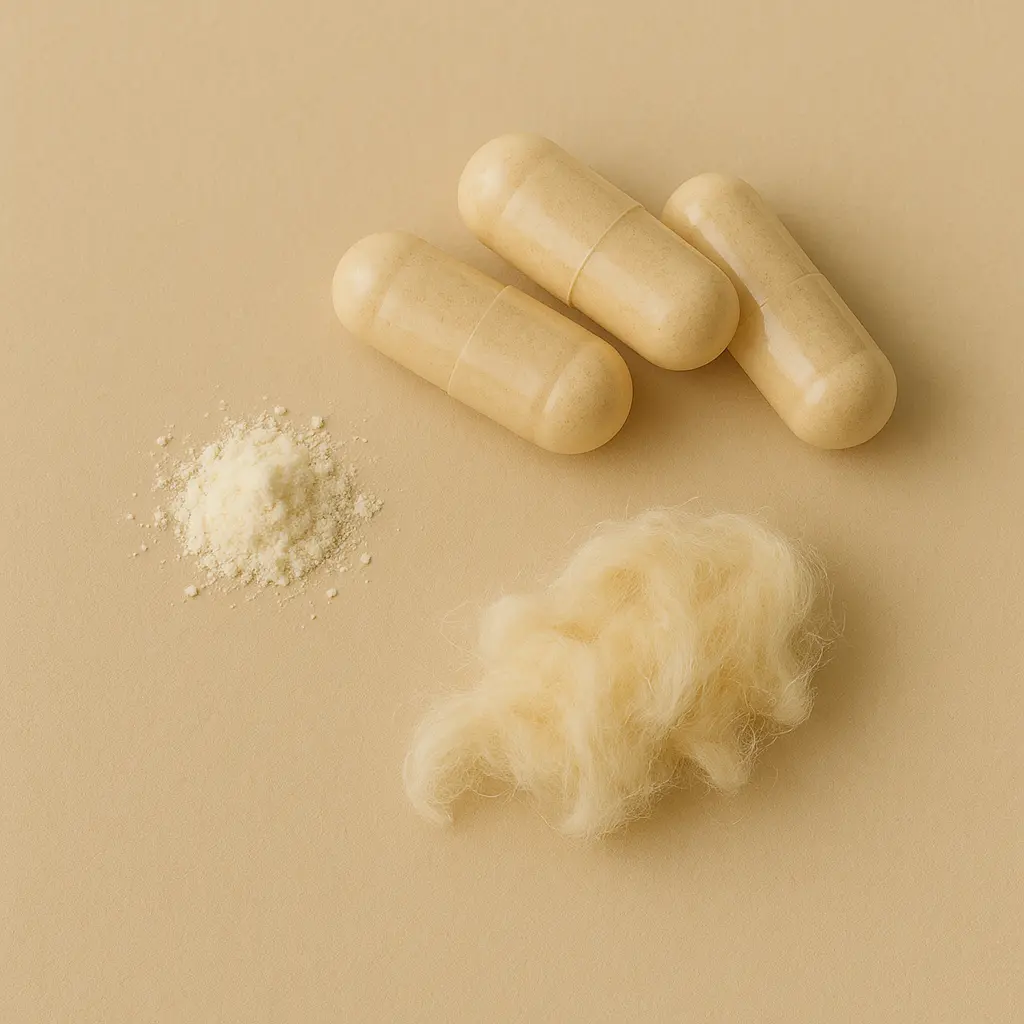

Vitamin D3 (Lanolin) 25 µg

| Vitamin | Vitamin D3 (cholecalciferol) from lanolin | 25.0 µg | 50 |

Capsules Ingredients: Vegan material